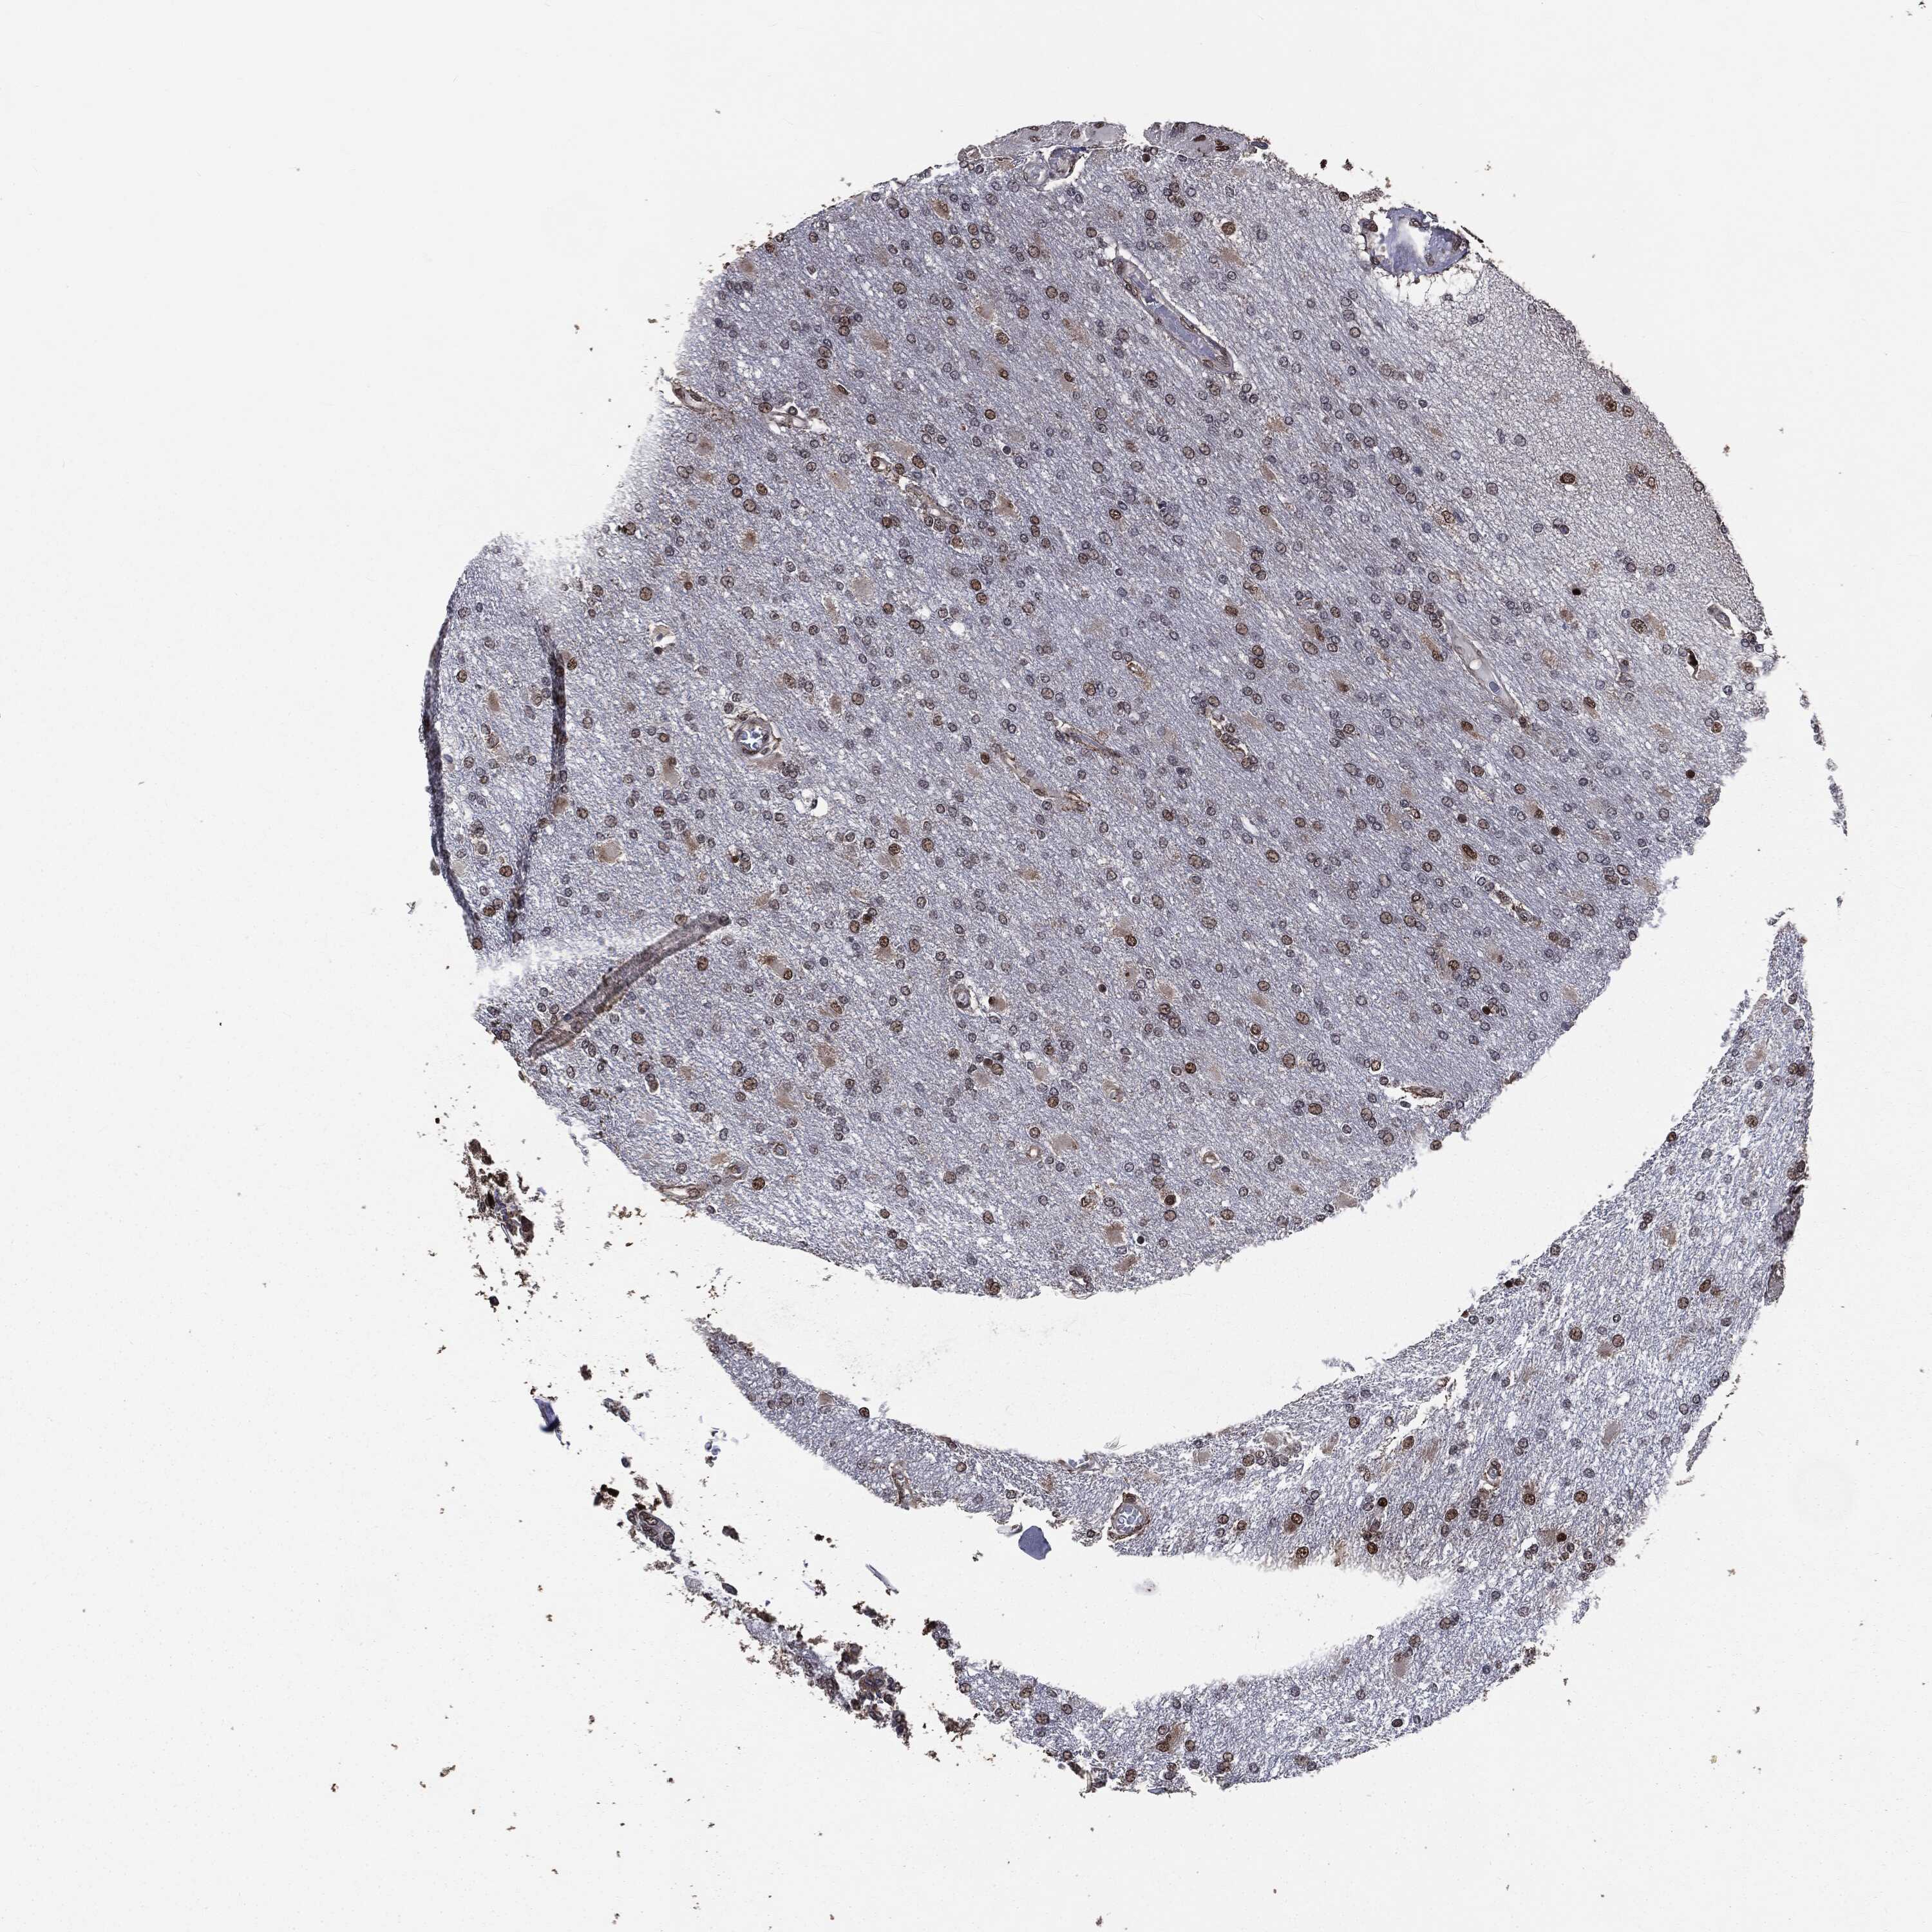

GLIOMA - Protein expressioni

A mouse-over function shows sample information and annotation data. Click on an image to view it in a full screen mode. Samples can be filtered based on level of antibody staining by selecting one or several of the following categories: high, medium, low and not detected. The assay and annotation is described here.

Note that samples used for immunohistochemistry by the Human Protein Atlas do not correspond to samples in the TCGA dataset.

Antibody stainingi

Antibody staining in the annotated cell types in the current human tissue is reported as not detected, low, medium, or high, based on conventional immunohistochemistry profiling in selected tissues. This score is based on the combination of the staining intensity and fraction of stained cells.

Each image is clickable and will lead to virtual microscopy that enables deeper exploration of all samples and also displays staining intensity scores, fraction scores and subcellular localization as well as patient and tissue information for each sample.

Antibody HPA022914

Antibody HPA064732

Staining

High

Medium

Low

Not detected

Intensity

Strong

Moderate

Weak

Negative

Quantity

>75%

75%-25%

<25%

None

Location

Nuclear

Cytoplasmic/membranous

Cytoplasmic/membranous,nuclear

Glioma, malignant, High grade

Glioma, malignant, Low grade

Glioma, malignant, NOS